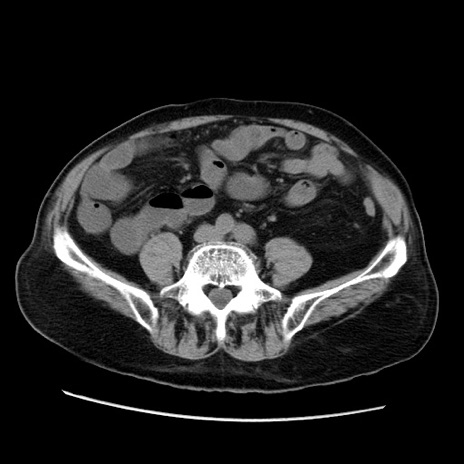

症例21(横断像)

【症例】70歳代男性

【主訴】腹痛

【現病歴】肝硬変・肝細胞癌にてかかりつけの方。約9時間前に食後より腹痛出現。症状が徐々に増悪し、嘔吐出現したため来院。

【既往歴】肝硬変、肝細胞癌(RFA、TACE後)

【身体所見】意識清明、表情苦悶様、BT 36℃、BP 129/78mmHg、P 88bpm、SpO2 97%(RA)、右上腹部から心窩部にかけて圧痛あり、反跳痛なし、筋性防御あり。

【データ】WBC 5800、CRP 0.16